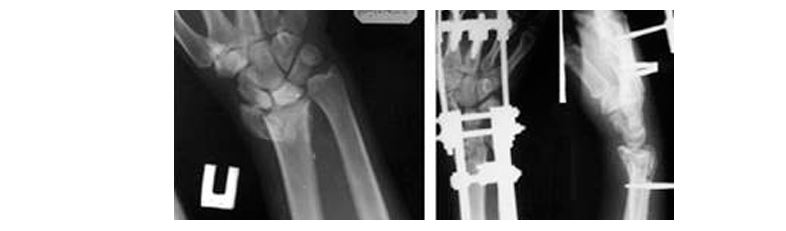

Навчання проводили одні із найкращіх фахівці у сфері ортопедії та травматології, зокрема доктор медичних наук, професор, провідний науковий співробітник відділу мікрохірургії та реконструктивної хірургії кисті ДУ “Інститут травматології та ортопедії НАМН України”, м. Київ І.М Курінний (“Переломи кісток передпліччя).

Актуальні питання хірургічного лікування та реабілітації”); кандидат медичних наук, доцент кафедри травматології та ортопедії НМУ П.В Нікітін (“Переломи дистального метаепіфіза променевої кістки. Сучасні підходи та принципи хірургічного лікування”); кандидат медичних наук, асистент кафедри травматології та ортопеді НМУ М.А.Циганков (“Переломи кісток зап’ястка та кисті. Сучасні стратегії консервативного та хірургічного лікування”).